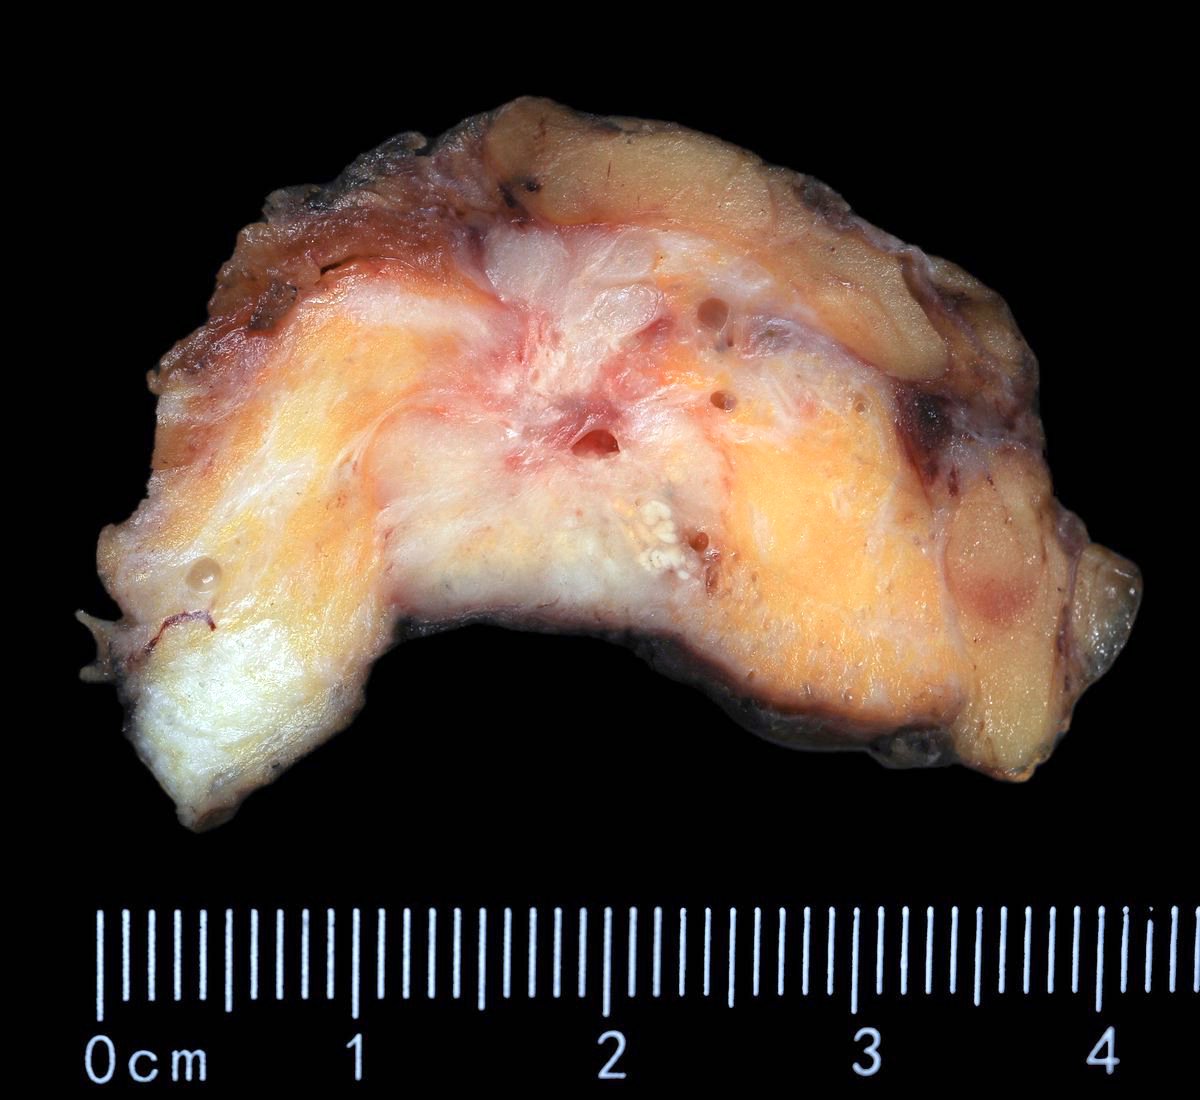

Gross description

- Grossly evident mass, with an irregular, stellate outline or nodular configuration

- Mass is usually poorly circumscribed and contracts from surrounding tissue

- Firm or even hard on palpation and may have a gritty feel when cut with a knife, grating sound when scraped

- May show streaks of chalky white elastotic stroma penetrating surrounding stroma (crab-like), calcification

- Large tumors have hemorrhage, necrosis and cystic degeneration

- May be fixed to chest wall and cause skin dimpling or nipple retraction

- Some tumors, including neoadjuvant treated cancers, may be grossly inapparent and require careful correlation with the imaging at the time of gross examination and tissue sampling